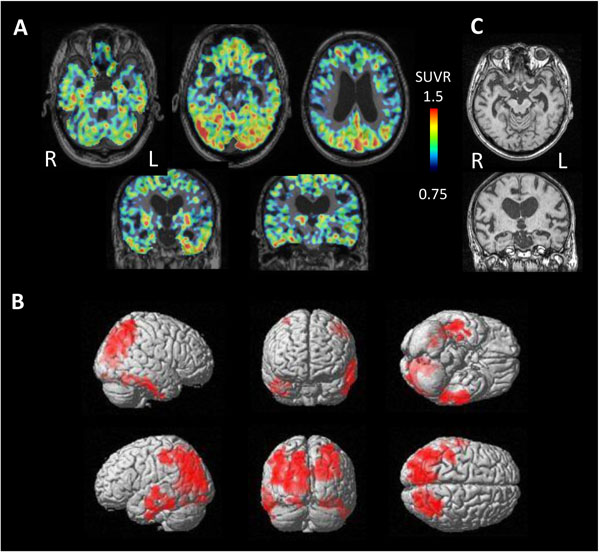

3.5. Subtypes of ANDE

Four cases were diagnosed as having AGD based on clinical course and neuroimaging findings. These cases showed significantly high tau accumulation on either side of the temporal lobe (Fig. 6). The side of higher tau accumulation was on the atrophied side in 3 of 4 cases, suggesting the dominantly affected side.

In contrast, 3 cases of NFTPD revealed tau accumulation on the bilateral temporal lobes and parietal lobes (Fig. 7). MRI showed mild atrophy on the bilateral parahippocampal gyrus.

4.2. Pathological Mechanisms for Tau Accumulation

An autopsy was obtained in only 1 case, in which neurofibrillary tangles were observed at the parahippocampal gyrus. [11C]PBB3-PET also revealed tau accumulation in the same lesion. Three cases of clinical NFTPD showed significant [11C]PBB3 accumulation at lateral temporal lobe. These are the typical distributions of neurofibrillary tangle in NFTPD, suggesting the possibility that [11C]PBB3 detects tau in the neurofibrillary tangle in these cases.